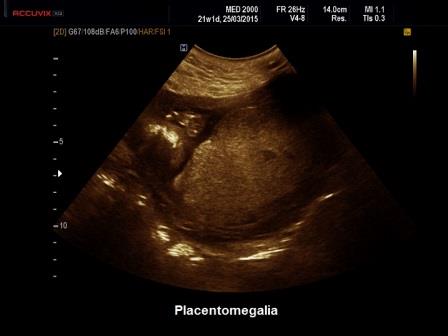

Il normale spessore della placenta viene calcolato considerando che la placenta cresce di spessore di circa 1 mm. a settimana. Un aumento di spessore della placenta si diagnostica se lo spessore della placenta supera i 4 cm. nel corso del II trimestre e i 6 cm. nel corso del III trimestre (Norton ME et al. Callen Ultr Obst Gyn 19:685-715. Elsevier 2017)

Un

aumento di spessore della placenta (Placentomegalia) può

riconoscere varie cause che vengono distinte in due categorie in base alla ecostruttura: